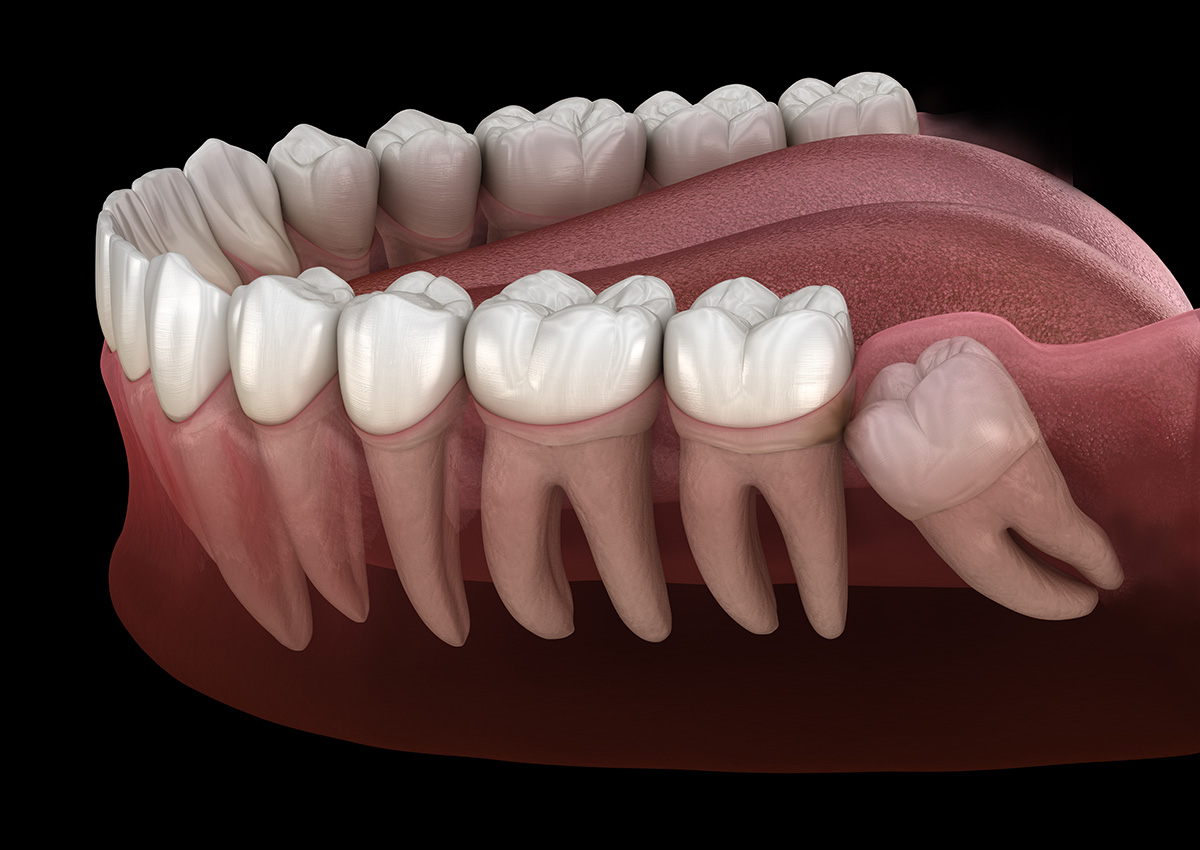

The most common reason for wisdom teeth extractions is insufficient space in the mouth. When there is not enough room for the wisdom teeth to emerge properly, they may become impacted, meaning they cannot fully break through the gum line. Impacted wisdom teeth can lead to various issues, including pain, infection, and damage to neighboring teeth.

Wisdom teeth may erupt at awkward angles or positions, causing them to press against neighboring teeth. This misalignment can result in crowding and disrupt the alignment of your existing teeth.

Wisdom teeth, also called third molars, are the last permanent teeth to develop and typically emerge in the late teens to early twenties. They can erupt normally in some patients, but many people have jaws that are too small to accommodate these additional molars. When wisdom teeth cannot erupt fully or come in at an awkward angle, they may become impacted and create pressure on surrounding structures.